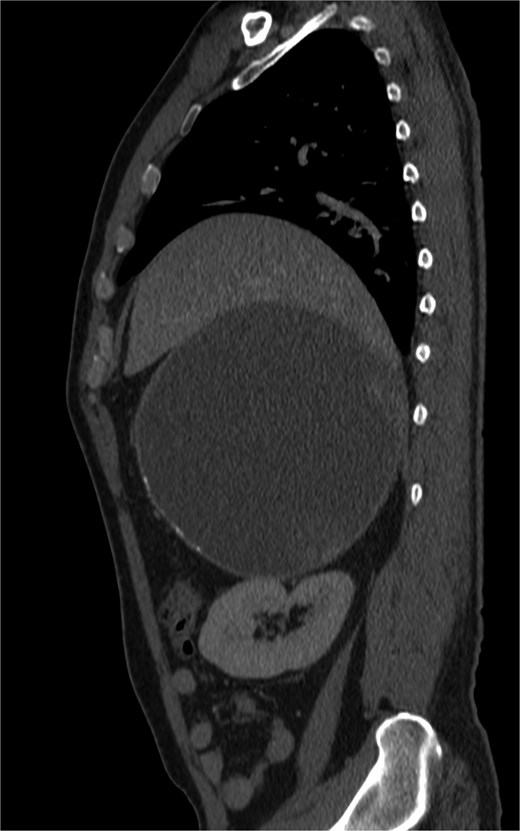

Positron-emission tomography (PET) scan with F18-Fluorodeoxy-glucose (FDG) and C11-Acetate, and combined contrast-enhanced computerized tomography (CT) revealed a predominantly cystic mass measuring ~14.8 × 17.9 × 18.6 cm located on the right side of the abdomen, arising from the retroperitoneal space with close approximation to the adrenal gland. It displaced the adjacent organs, including pancreas and the right kidney; A tiny mural calcification and focal hypermetabolic activity within the cyst wall raised the possibility of malignant transformation (Figs 1–4).

Cystic mass with mural calcification and tissue components in the posteroinferior portion, closely abutting the right kidney and adrenal.